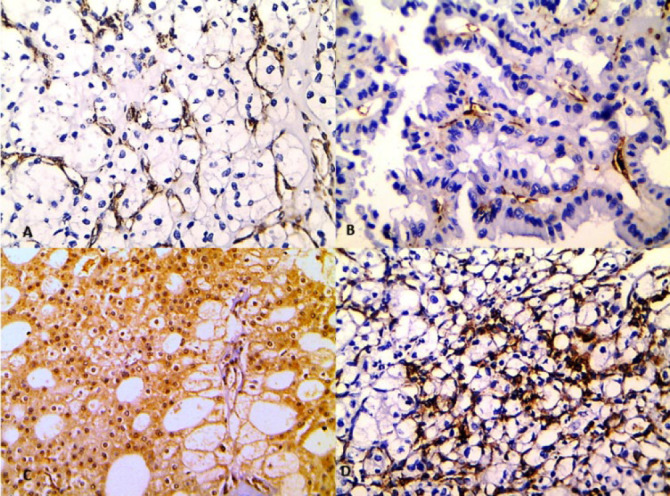

Methods: This retrospective study included sixty cases of RCC after obtaining ethical approval. Sections were immunohistochemically stained by Nestin and FLT1 then their expressions were compared to different clinicopathological parameters. MVD was evaluated using Nestin and CD34 and compared to the different parameters.

Results: Nestin was expressed mainly in endothelial cells of small vessels in 65% of cases while FLT1 was expressed in tumor and endothelial cells in 73.3% of cases. Their expressions were significantly associated with aggressive tumor parameters including larger tumors, high-grade tumors, wider tumor extension, and advanced stage. Moreover, Nestin expression was significantly associated with metastasis. MVD evaluated by Nestin showed more associations with larger tumors, high-grade tumors, wider tumor extension, advanced stage, and metastasis than MVD measured by CD34. Nestin and FLT1 positivity and high MVD measured by Nestin were significantly associated with short overall survival.